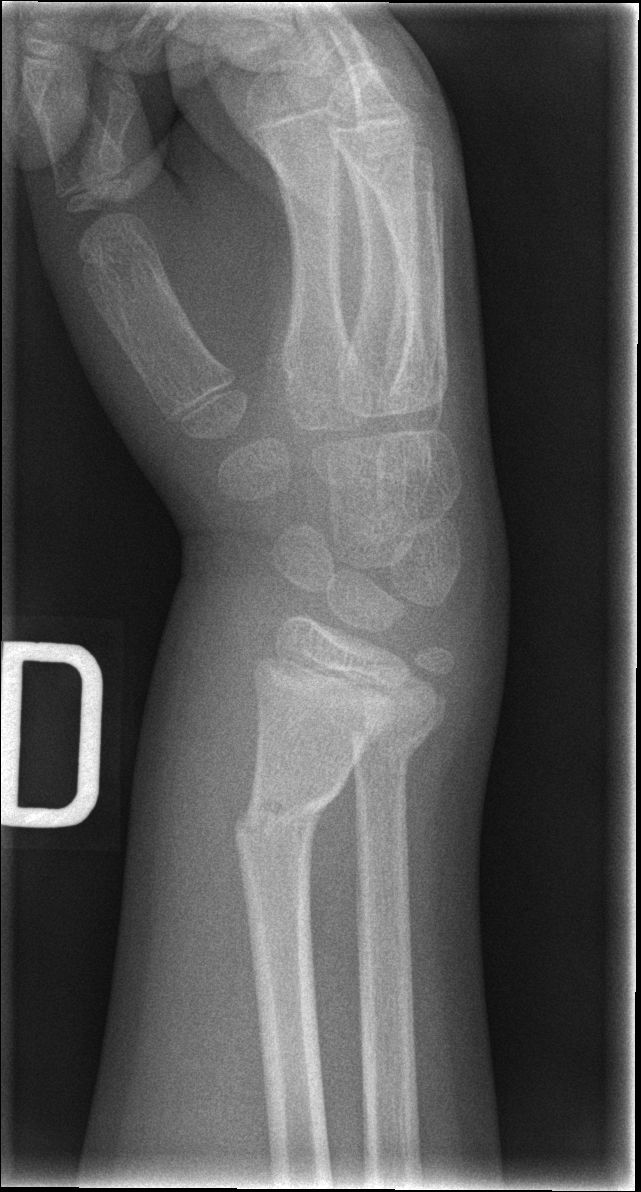

3 Published on 7 juillet 2015 in La fracture d’AmélianePleine résolution (641 × 1192) ← Précédent Suivant →